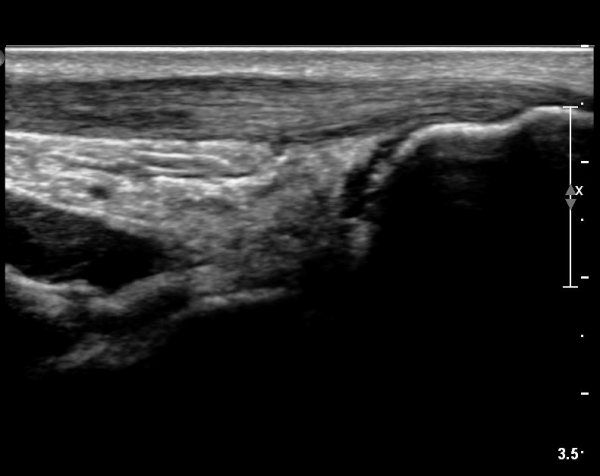

[¹ß¸ñ] simultaneosus tear of GCM and achiles tendon

abrupt leg pain developed during foot volleyball

he walk with severe limping with no weight bearing on rt. leg. on examination, there is local tendernes at GCM and achiles tendon, severe pain with ankle dorsiflexion.

ÃÊÀ½ÆÄ °Ë»ç